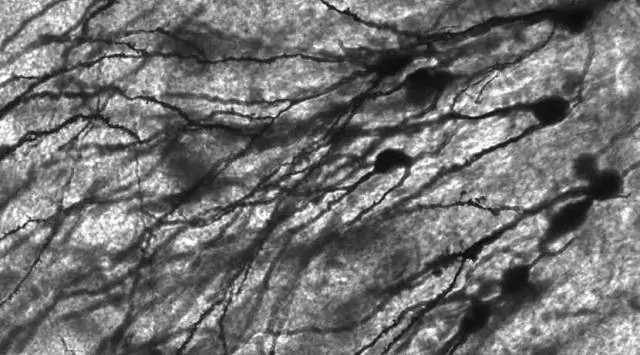

Исследователи до настоящего времени сосредоточились на белковых «метках», обнаруженных на внешних мембранах митохондрий, особенно на белке паркине, который прикрепляет эти метки, чтобы объяснить, как деградирующие органеллы клетки, называемые аутофагосомами, нацелены на больные митохондрии, объяснил доктор. Левин, заведующий почетной кафедрой биомедицинских наук имени Чарльза Кэмерона Спрэга. (Аутофагосомы представляют собой двухмембранные везикулы, содержащие клеточный материал, подлежащий деградации в процессе, называемом аутофагией.)

В ходе исследования исследователи обнаружили, что белок под названием запретин 2 (PHB2) находится на внутренней мембране митохондрий, но обнажается, когда внешняя мембрана больной митохондрии разрывается. Как только происходит разрыв, белок LC3, который скользит по внешней стороне аутофагосомы как наблюдатель, притягивается к PHB2.

Белок LC3 затем присоединяется к PHB2, и аутофагосома переносит свой обреченный груз в лизосому - еще одну органеллу, обнаруженную внутри клеток, - которая действует как крошечный желудок с ферментами для расщепления клеточных отходов.